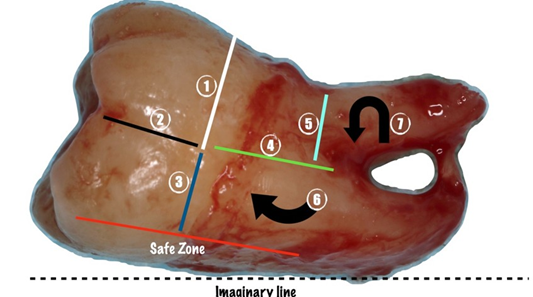

Surgical Technique

The teeth were extracted under local anesthesia (4% articaine with 1:100000 epinephrine), followed by a sulcular incision from the mesiobuccal part of the second molar to 1.5 cm distally along the mandibular ramus. Careful elevation of the mucoperiosteal flap was performed. With a high-speed bur under irrigation with saline solution or with piezosurgery, bone around the crown of the tooth was removed up to the enamel-cementum junction. Then, using a high-speed contra-angle handpiece and a carbide bur, the tooth was sectioned under irrigation with physiological saline. In the experimental group, the upper part of the crown was first sectioned halfway through its depth with a horizontal cut; then the upper crown segment was fractured using a straight elevator. Afterwards, the lower part of the crown was further sectioned using the bur, creating an imaginary line at the bottom of the tooth that serves as a barrier to protect the nerve. The bone is not drilled beyond this depth. The crown segment is then fractured and removed with the elevator. Once the crown is sectioned, a straight elevator is used to check for movement of the root block by placing the tip between the bone and the tooth. If the root block moves, extraction is attempted with the elevator. If no movement occurs, the roots are sectioned in the middle, and the straight elevator is used again to check for luxation by inserting the tip between the bone and the root. If luxation occurs, the root that is positioned higher is removed first, followed by the lower one. If there is no luxation, the upper root segment in the visible area is sectioned and removed, followed by the removal of the lower root with the elevator, and finally, the upper root is removed with a triangular elevator (Figure 1).

Figure 1: “Cut as you go” technique.